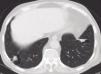

For the last 8 months, the patient had had a dry cough, accompanied by asthenia, anorexia and a weight loss of 6 kilograms. In view of the constitutional syndrome with cough, outpatient investigations had been undertaken, showing an initial creatinine level of 3.5mg/dL, which increased to 4.9mg/dL 10 days later. Renal ultrasound revealed normalsized kidneys with correct corticomedullary differentiation, and a thoracic CT scan showed lesions compatible with two pulmonary masses. One was located in the anterobasal segment of the left lower lobe (LLL) and measured approximately 5 × 4cm. The other was located in the posterobasal segment of the right lower lobe (RLL), measured approximately 4 × 3cm, had poorly-defined edges, and an air bronchogram in its interior. There was also slight peripheral infiltrate in the apical region of the RLL, with a non-specific inflammatory appearance. Another finding of note was the presence of mediastinal lymphadenopathies. A bronchoscopy was then performed, showing moderate infiltration of the subsegmental spur of the right basal segment, which was biopsied. Bronchial aspirate samples were taken for microbiology and cytology. Ziehl-Neelsen staining was negative. An attempt to perform a fine-needle aspiration biopsy of one of the pulmonary masses was unsuccessful due to technical problems; therefore, an in-patient mediastinoscopy was arranged with the Thoracic Surgery Department.

The protein analysis showed beta-gamma bridging. The bone marrow aspirate ruled out monoclonal gammopathies. We repeated the thoracic CT scan and confirmed the previously described pulmonary nodular images and mediastinal lymphadenopathies. The thoracic surgeons performed a mediastinoscopy with lymph node biopsy; lymphomatous disease was ruled out in the histology report.